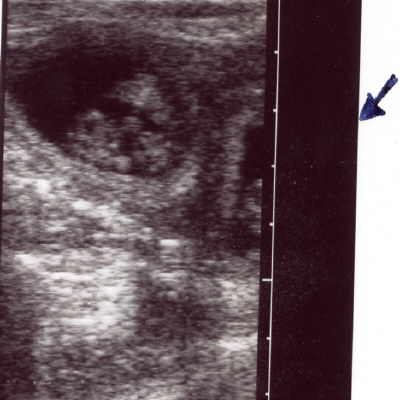

Und so sieht das in einem Havi von Innen aus:

Ultraschall 3.-4. Woche

Nicht zu fassen; schaut einmal. So sehen meine Welpen auf einem Ultraschallbild nach nicht ganz vier Wochen Trächtigkeit aus. Wenn Ihr genau hinseht, sehr Ihr links die Fruchthülle mit einem Welpen. Rechts kann man einen zweiten Welpen vermuten. Die ganze Fruchtblase misst gerade mal 2,5 cm. Es könnten derzeit auch kleine Dinosaurier, ein Menschenbaby oder andere Wesen sein. Man kann halt noch nicht gut sehen, dass hier ein kleines Haviwunder entsteht. 😊